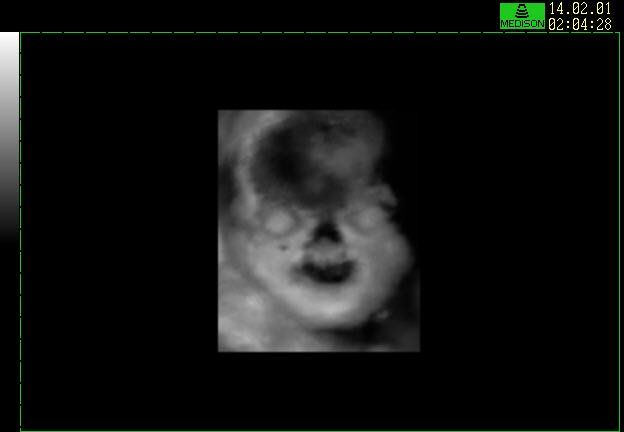

An approx. 12 week fetus, first ultrasound of this pregnancy.